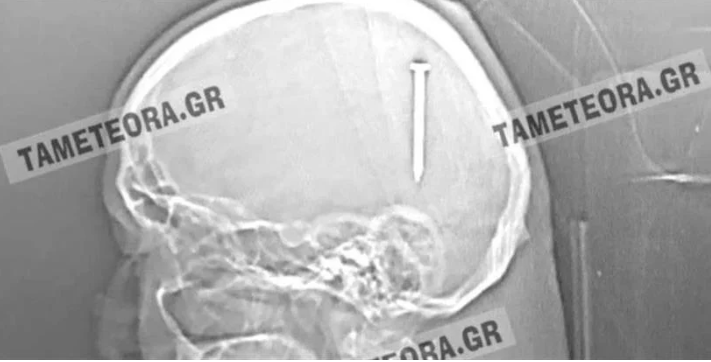

Από θαύμα ζει ένας κάτοικος της Καλαμπάκας, καθώς βρέθηκε ξαφνικά με… ένα καρφί 5 εκατοστών σφηνωμένο στο κεφάλι του!

Σύμφωνα με το tameteora.gr, εκτός από το αρχικό τράνταγμα που ένιωσε κατά τη διάρκεια εργασιών που έκανε, ο άνδρας δεν ένιωσε πόνο ούτε είχε κάποιο άλλο σύμπτωμα.

Ο άνδρας μεταφέρθηκε αρχικά στο Κέντρο Υγείας Καλαμπάκας, στη συνέχεια στο Γενικό Νοσοκομείο Τρικάλων και από εκεί στο Πανεπιστημιακό Νοσοκομείο Λάρισας, όπου υποβλήθηκε σε επέμβαση και του αφαιρέθηκε το καρφί με επιτυχία.

Ο άνδρας αναρρώνει υπό την παρακολούθηση των γιατρών, αλλά εκτιμάται ότι δεν διατρέχει κανέναν κίνδυνο η υγεία του.

Πρόκειται πραγματικά για ένα σπανιότατο περιστατικό, καθώς αν το καρφί βρισκόταν ελάχιστα χιλιοστά από το σημείο που σφηνώθηκε, θα ήταν πολύ επικίνδυνο για την υγεία του.